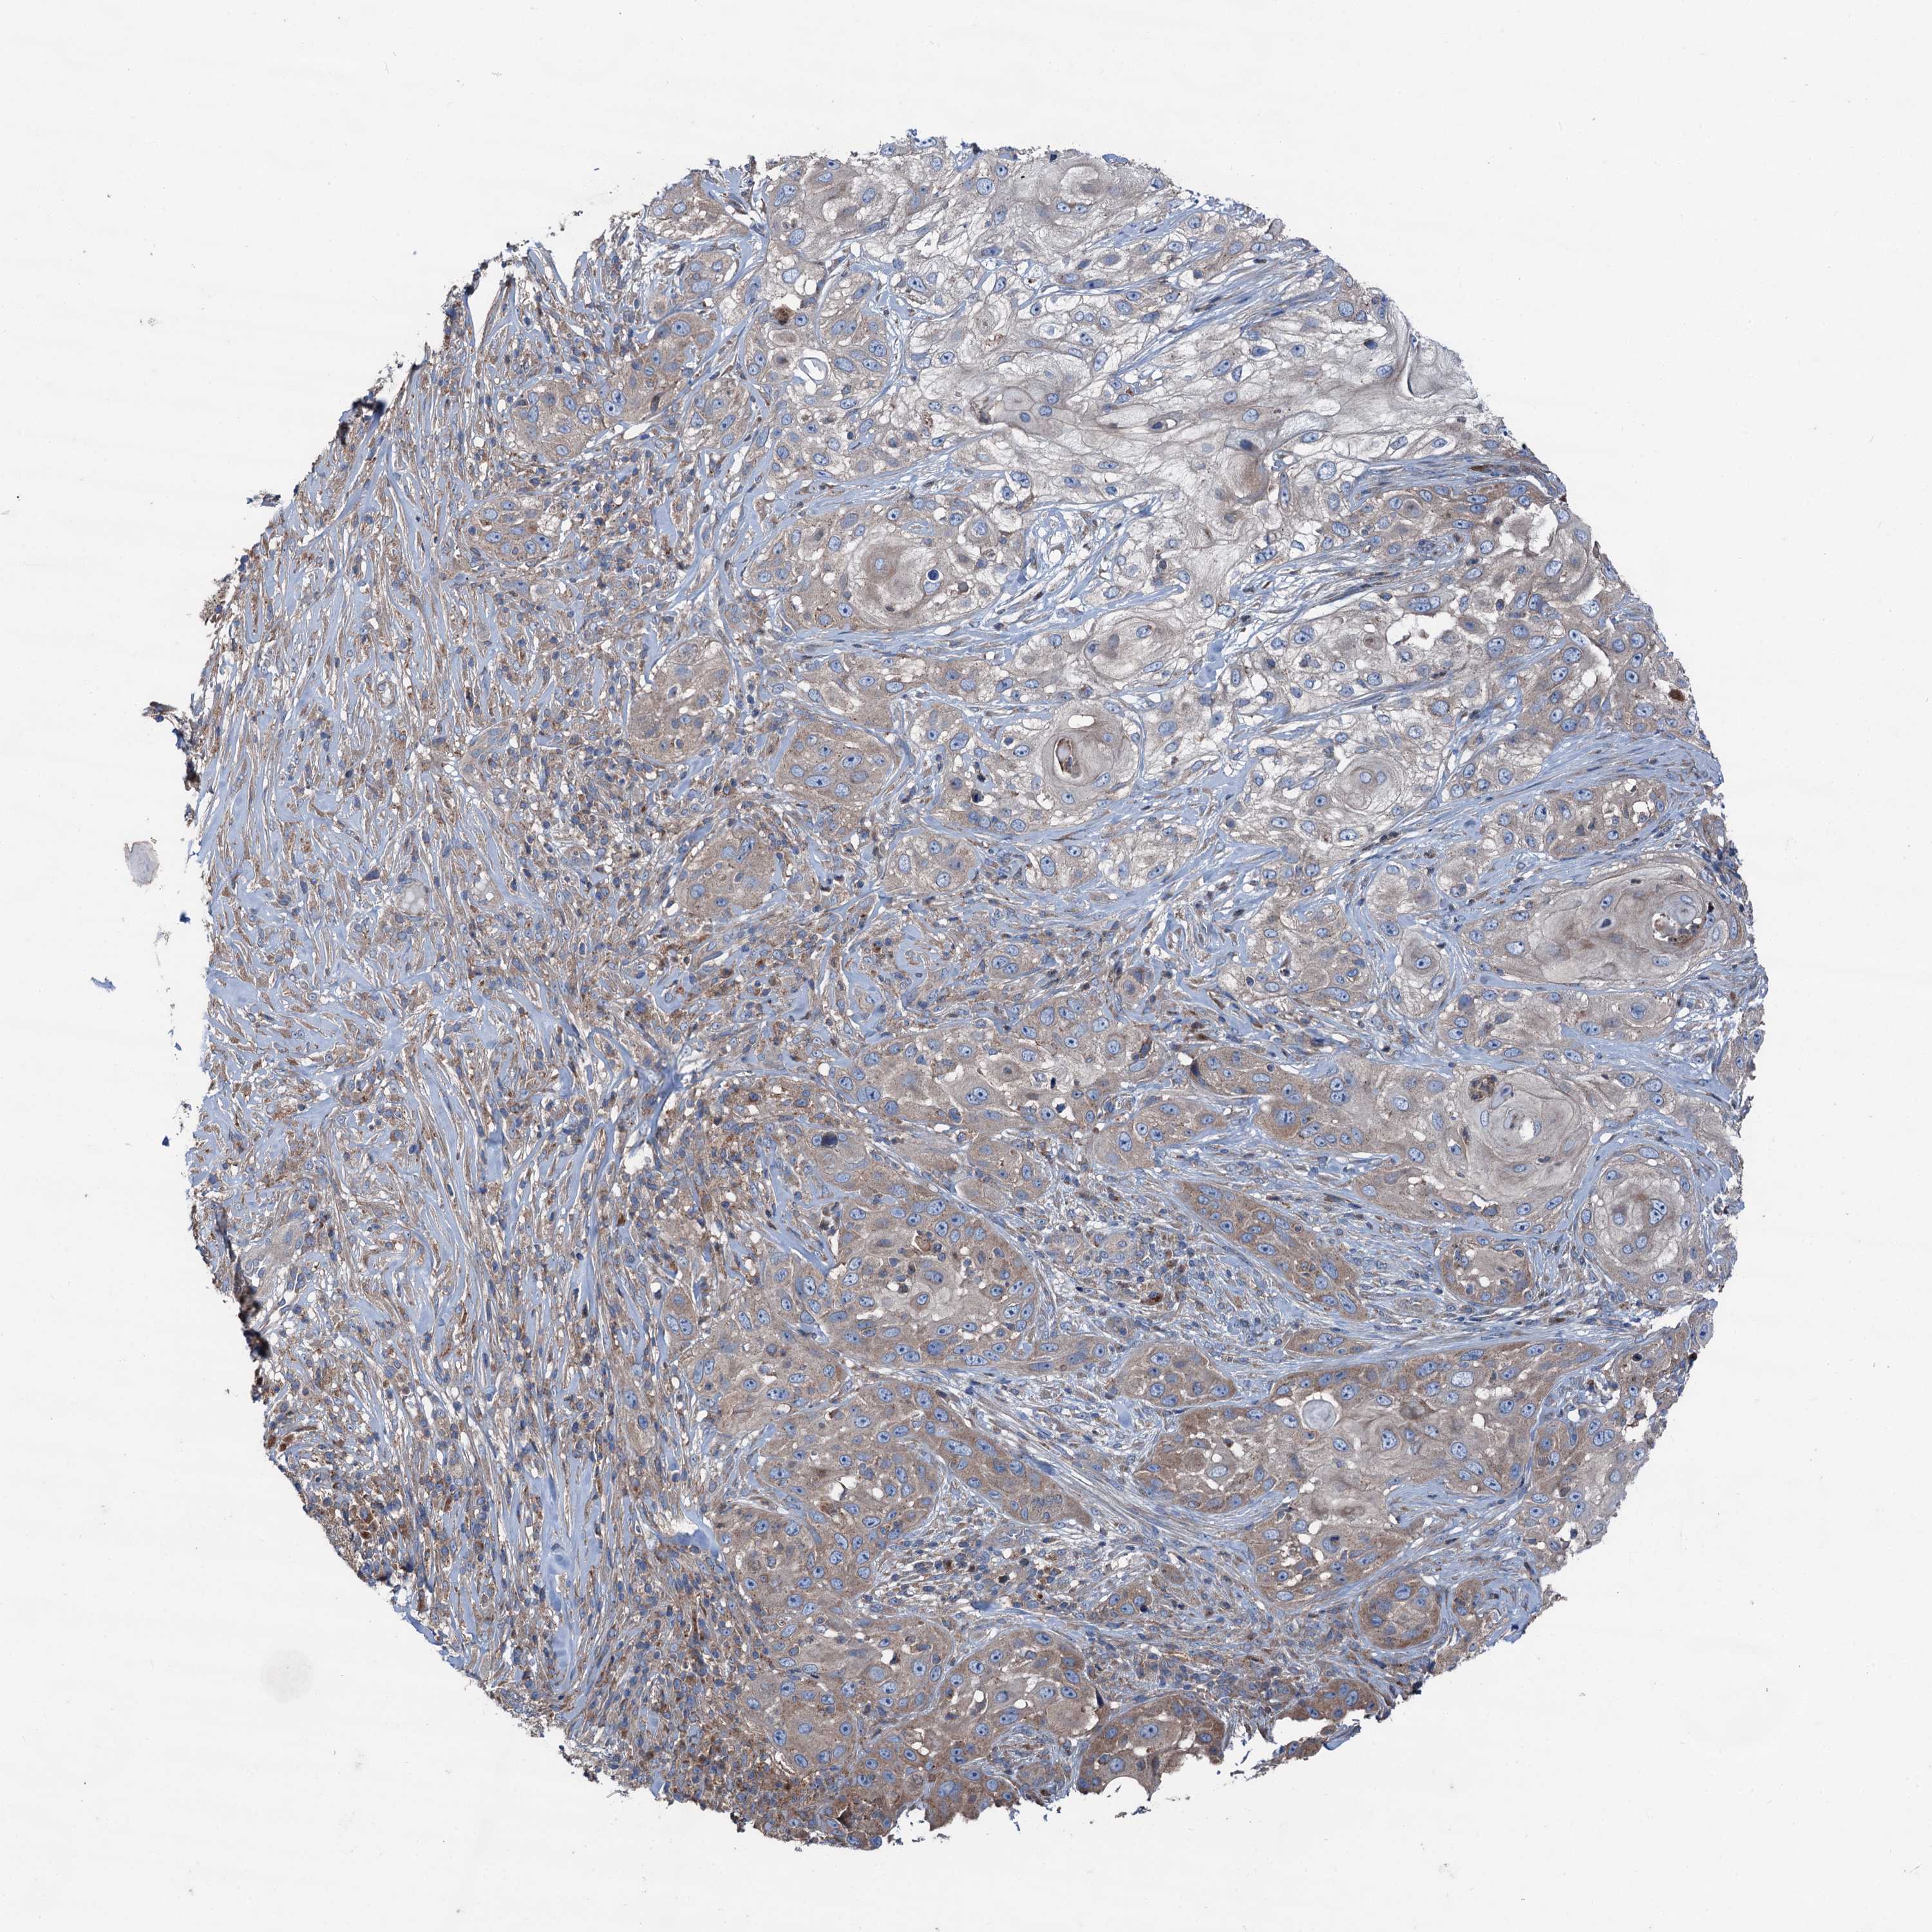

SKIN CANCER - Protein expressioni

A mouse-over function shows sample information and annotation data. Click on an image to view it in a full screen mode. Samples can be filtered based on level of antibody staining by selecting one or several of the following categories: high, medium, low and not detected. The assay and annotation is described here.

Each image is clickable and will lead to virtual microscopy that enables deeper exploration of all samples and also displays staining intensity scores, fraction scores and subcellular localization as well as patient and tissue information for each sample.

Antibody HPA038804

Staining

High

Medium

Low

Not detected

Intensity

Strong

Moderate

Weak

Negative

Quantity

>75%

75%-25%

<25%

None

Location

Nuclear

Cytoplasmic/membranous

Cytoplasmic/membranous,nuclear

Basal cell carcinoma

Squamous cell carcinoma, NOS

Squamous cell carcinoma, metastatic, NOS